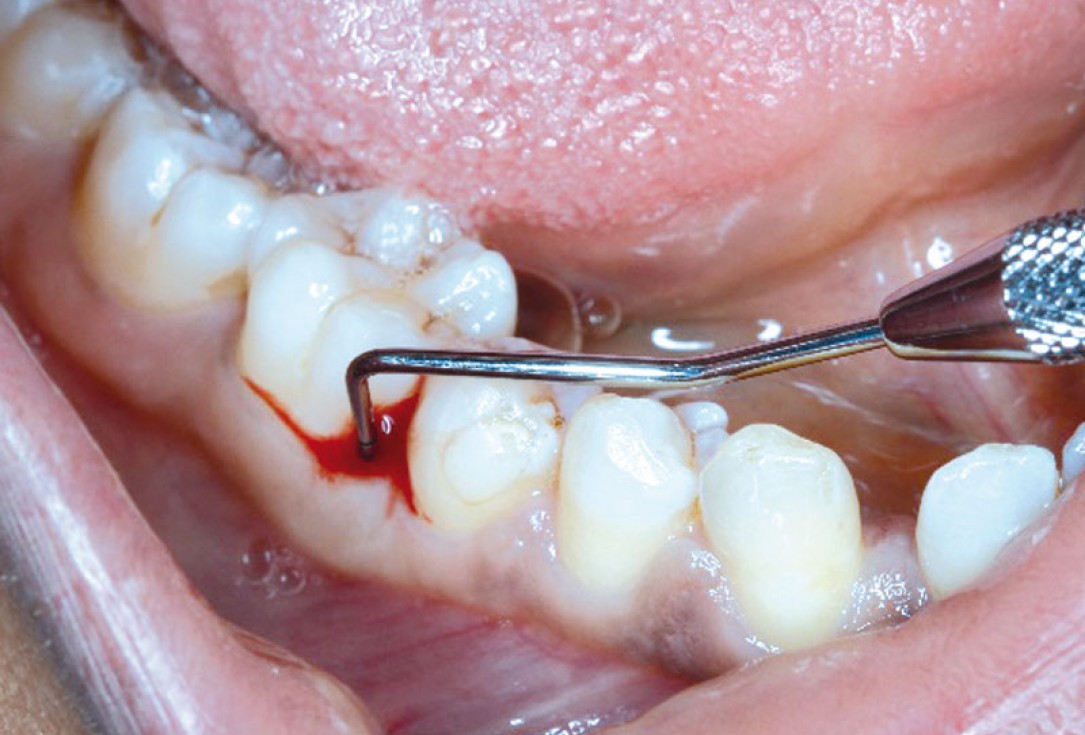

Intrabony defect treated using collprotect® membrane & cerabone® (1) - Cosgarea & Sculean

Pre-surgical probing reveals a deep intrabony defect on the distal aspect of the upper canine.